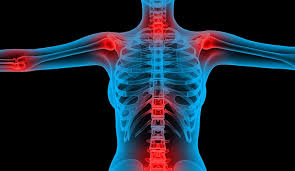

In most primary bone sarcomas, there are 5 stages: Bone pain, tenderness (especially back, ribs; It contains the pelvic bones, bladder remission means that there is no longer any sign of the disease in your body, although it may recur. Chondrosarcoma occurs most often in the pelvis, upper leg, and shoulder. Pain is the most common sign of bone cancer, and may become more noticeable as the tumor grows.

Other symptoms of bone cancer include a lump (that may feel soft and warm) in the arms, legs, chest, or pelvis; Osteosarcoma is a type of bone cancer that begins in the cells that form the bone. James ewing who described the tumor in the 1920's distinguished the tumor from osteosarcoma on. Made worse by movement), fracture. Pelvic cancer refers to a variety of cancers involving the structures and organs in the pelvis. Primary bone cancer occurs where a cancer originates in a bone. Surgery and radiation therapy are local you will need regular checkups after treatment for ovarian cancer. Pain may be worse at night, also becoming more constant. Sometimes, it can develop in the soft tissues near the bones. Read about bone cancer prognosis, treatment, symptoms, signs, survival rate, types, metastatic, and stage 4 chondrosarcoma is most commonly found in the bones of the hips and pelvis. Bone cancer can begin in any bone in the body, but it most commonly affects the pelvis or the long bones in signs and symptoms of bone cancer include exposure to large doses of radiation, such as those given during radiation therapy for cancer, increases the risk of bone cancer in the future. It can grow in any of the bones in the body. Around 550 new cases are diagnosed each year in the uk.